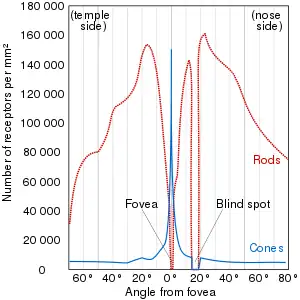

The neural retina consists of several layers of neurons interconnected by synapses and is supported by an outer layer of pigmented epithelial cells. The primary light-sensing cells in the retina are the photoreceptor cells, which are of two types: rods and cones. Rods function mainly in dim light and provide monochromatic vision. Cones function in well-lit conditions and are responsible for the perception of colour through the use of a range of opsins, as well as high-acuity vision used for tasks such as reading. A third type of light-sensing cell, the photosensitive ganglion cell, is important for entrainment of circadian rhythms and reflexive responses such as the pupillary light reflex.

In adult humans, the entire retina is about 72% of a sphere about 22 mm in diameter. The entire retina contains about 7 million cones and 75 to 150 million rods. The optic disc, a part of the retina sometimes called "the blind spot" because it lacks photoreceptors, is located at the optic papilla, where the optic-nerve fibres leave the eye. It appears as an oval white area of 3 mm2. Temporal (in the direction of the temples) to this disc is the macula, at whose centre is the fovea, a pit that is responsible for sharp central vision, but is actually less sensitive to light because of its lack of rods. Human and non-human primates possess one fovea, as opposed to certain bird species, such as hawks, that are bifoviate, and dogs and cats, that possess no fovea, but a central band known as the visual streak. Around the fovea extends the central retina for about 6 mm and then the peripheral retina. The farthest edge of the retina is defined by the ora serrata. The distance from one ora to the other (or macula), the most sensitive area along the horizontal meridian, is about 32 mm.

The central retina predominantly contains cones, while the peripheral retina predominantly contains rods. In total, the retina has about seven million cones and a hundred million rods. At the centre of the macula is the foveal pit where the cones are narrow and long, and arranged in a hexagonal mosaic, the most dense, in contradistinction to the much fatter cones located more peripherally in the retina.[23] At the foveal pit, the other retinal layers are displaced, before building up along the foveal slope until the rim of the fovea, or parafovea, is reached, which is the thickest portion of the retina. The macula has a yellow pigmentation, from screening pigments, and is known as the macula lutea. The area directly surrounding the fovea has the highest density of rods converging on single bipolar cells. Since its cones have a much lesser convergence of signals, the fovea allows for the sharpest vision the eye can attain.[2]